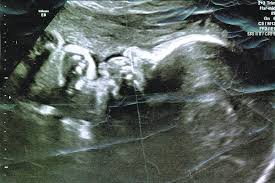

The nuchal translucency screening, or nt, is a prenatal ultrasound test that can help to determine the fetus's likelihood of having down syndrome or some other chromosome abnormality. What do ultrasound abbreviations and initials mean? This test measures the size of the clear tissue, called the nuchal translucency, at the back of your. A look at what your scans will involve. The nuchal translucency scan (also called the nt scan) uses ultrasound to assess your developing baby's risk of having down syndrome (ds) and some other chromosomal abnormalities, as well as major congenital heart problems. A nuchal translucency (nt) ultrasound measures the fluid at the back of a baby's neck between 11 and 14 weeks of pregnancy. Nuchal translucency (nt) measures an area of fluid at the back of a baby's neck. Bookmerilab has partnered with many reputed and trusted.

A special ultrasound, called a nuchal translucency screening, measures the back of the baby's neck.

The ultrasound nt scan or nuchal translucency scan is an ultrasound to measure the amount of fluid that has been collected in the back of the neck of the fetus. A nuchal translucency (nt) ultrasound measures the fluid at the back of a baby's neck between 11 and 14 weeks of pregnancy. Nt focuses on a small, clear space at the back of a growing baby's neck called the nuchal fold. Major heart problems can also be detected using the nt prenatal test. Nuchal translucency (nt) normal range pregnancy is a time when people tend to learn a lot of new terminology. This is the ultrasound typically completed at the 12 week mark of pregnancy. The nuchal translucency screening, or nt, is a prenatal ultrasound test that can help to determine the fetus's likelihood of having down syndrome or some other chromosome abnormality. The amount of fluid is measured during an nt ultrasound scan: What do ultrasound abbreviations and initials mean? Nuchal translucency (nt) measurement nuchal translucensy (nt) is the clear space in the tissue of your developing baby's neck. Additional tests should be ordered by an ob or genetic counselor for confirmation. Ultrasound is a sound wave with a frequency higher than 20khz used to look at organs and structures inside the body. When there is more fluid than usual, it is called increased nuchal translucency or large